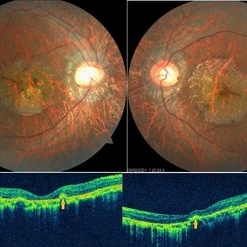

Multimodal Imaging in CHRPE

Multimodal Imaging in CHRPE

Mar 6 2025 by Gerardo - Montante Montelongo, MD

Fundus photograph of an 83-year-old male with a history of Diabetes, smoking, cataract surgery on the right eye in 2022, and open-angle glaucoma. Asymptomatic. Indirect ophthalmoscopy revealed 80% excavation, peripapillary atrophy, and a hyperpigmented perifoveal lesion with 35% atrophy, 10% drusen, and 5.1 mm diameter, corresponding to a CHRPE. At multimodal imaging, FFA shows hypoautofluorescence of the lesion, OCT shows preservation of internal retinal layers, atrophy of external retinal layer, with an RPE disruption, and posterior shadowing. USG shows a flat hyperechoic lesion 5.1 mm in diameter and 1.32 mm in thickness, solid and with high internal reflectance.

Photographer: Gerardo Montante-Montelongo, MD, Mexican Institute of Ophthalmology

Imaging device: Clarus 700

Condition/keywords: congenital hypertrophy of the retinal pigment epithelium (CHRPE), multimodal imaging